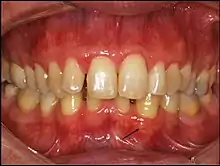

Gingival cyst of adult (arrow)

Panoramal radiograph of GCA. Inset: no evidence of bone involvement.

Gingival cyst of adult is a rare condition. The incidence is less than 0.5%. It is formed from the rests of dental lamina.[11] It is found in the soft tissues on the buccal and labial portions of the jaw. It usually occurs on the facial gingiva as a single small flesh colored swelling, sometimes with a bluish hue due to the cystic fluid. Sometimes, it may occur in cluster, either unilaterally or bilaterally or on the lingual surface of the alveolar process. It is most commonly seen in the canine and premolar regions of the mandible, and are sometimes confused with lateral periodontal cysts.[12] It is not normally problematic, but when it grows larger, it can cause some discomfort. It can be removed by simple surgical excision. They are developed late in life, generally up to the sixth decade of age.[1]